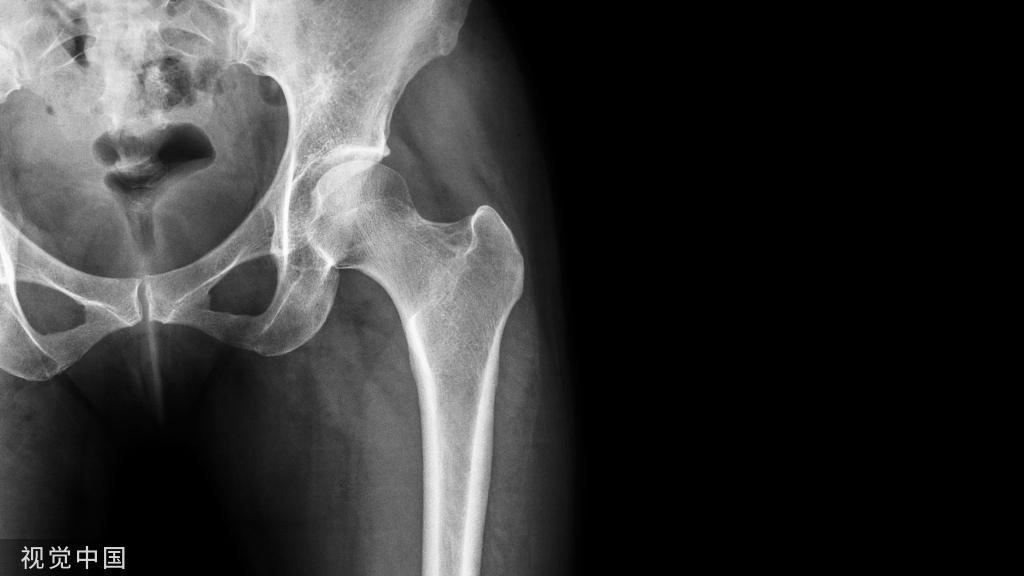

4.髋关节

在髂前上棘下方5 cm处,向上向后并稍向内进针(图4)。

也可紧依股骨大粗隆上缘上方,向内稍向上穿刺,针的方向可与股骨颈近乎平行(图4)。

图4 髋关节的穿刺 ①侧路;②前路